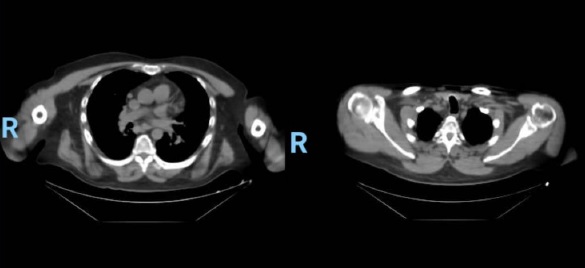

En la tomografía computada de tórax en ventana mediastínica se observan múltiples adenopatías localizadas en diversas áreas del cuello y mediastino. Estas adenopatías se distribuyen en las cadenas yúgulo-carotídeas, en ambas regiones supraclaviculares y a lo largo del mediastino, abarcando específicamente las siguientes áreas: la región paratraqueal superior derecha, los espacios retrocavo-pretraqueal y prevascular, la zona subcarinal, la ventana aortopulmonar y en la región de la arteria mamaria (AM). La presencia de estas adenopatías sugiere un compromiso linfático difuso en estas zonas.

La sarcoidosis pulmonar se caracteriza por varios hallazgos en la tomografía computarizada de alta resolución (TCAR). Estos incluyen linfadenopatía hiliar y paratraqueal bilateral bien definida, opacidades nodulares y micronodulares con distribución perilinfática. Los nódulos son redondeados y suelen tener un tamaño de 2 a 4 mm. También se observa el agrandamiento y calcificación de los ganglios linfáticos hiliares bilaterales. Las calcificaciones pueden presentar diferentes aspectos, como amorfo, puntiforme (parecido a una palomita de maíz) o similar a una cáscara de huevo. La distribución perilinfática de las lesiones micronodulares es el patrón parenquimatoso más frecuente. Con el tiempo, estas lesiones pueden fusionarse y formar macronódulos y conglomerados similares a masas, con la presencia de pequeños nódulos satélites alrededor de las masas conglomeradas, lo que se conoce como “signo de galaxia”.

En la TCAR se pueden encontrar otros hallazgos menos frecuentes, como cambios fibróticos con opacidades lineales y bronquiectasias por tracción, opacidades parcheadas en vidrio esmerilado, consolidación parcheada del espacio aéreo (alveolitis sarcoide o sarcoidosis alveolar), opacidades reticulares lineales aisladas, halo inverso o signo del atolón. La sarcoidosis pulmonar también muestra un patrón de atenuación en mosaico debido a la afectación granulomatosa o fibrosis de las vías respiratorias pequeñas, lo cual puede estar asociado con obstrucción en las pruebas de función pulmonar. El atrapamiento de aire es común pero no específico de la sarcoidosis y puede estar presente en cualquier etapa radiográfica de la enfermedad. Se detectan anomalías traqueobronquiales en la TC, con engrosamiento y estenosis de la pared bronquial, que se correlacionan con los hallazgos broncoscópicos.